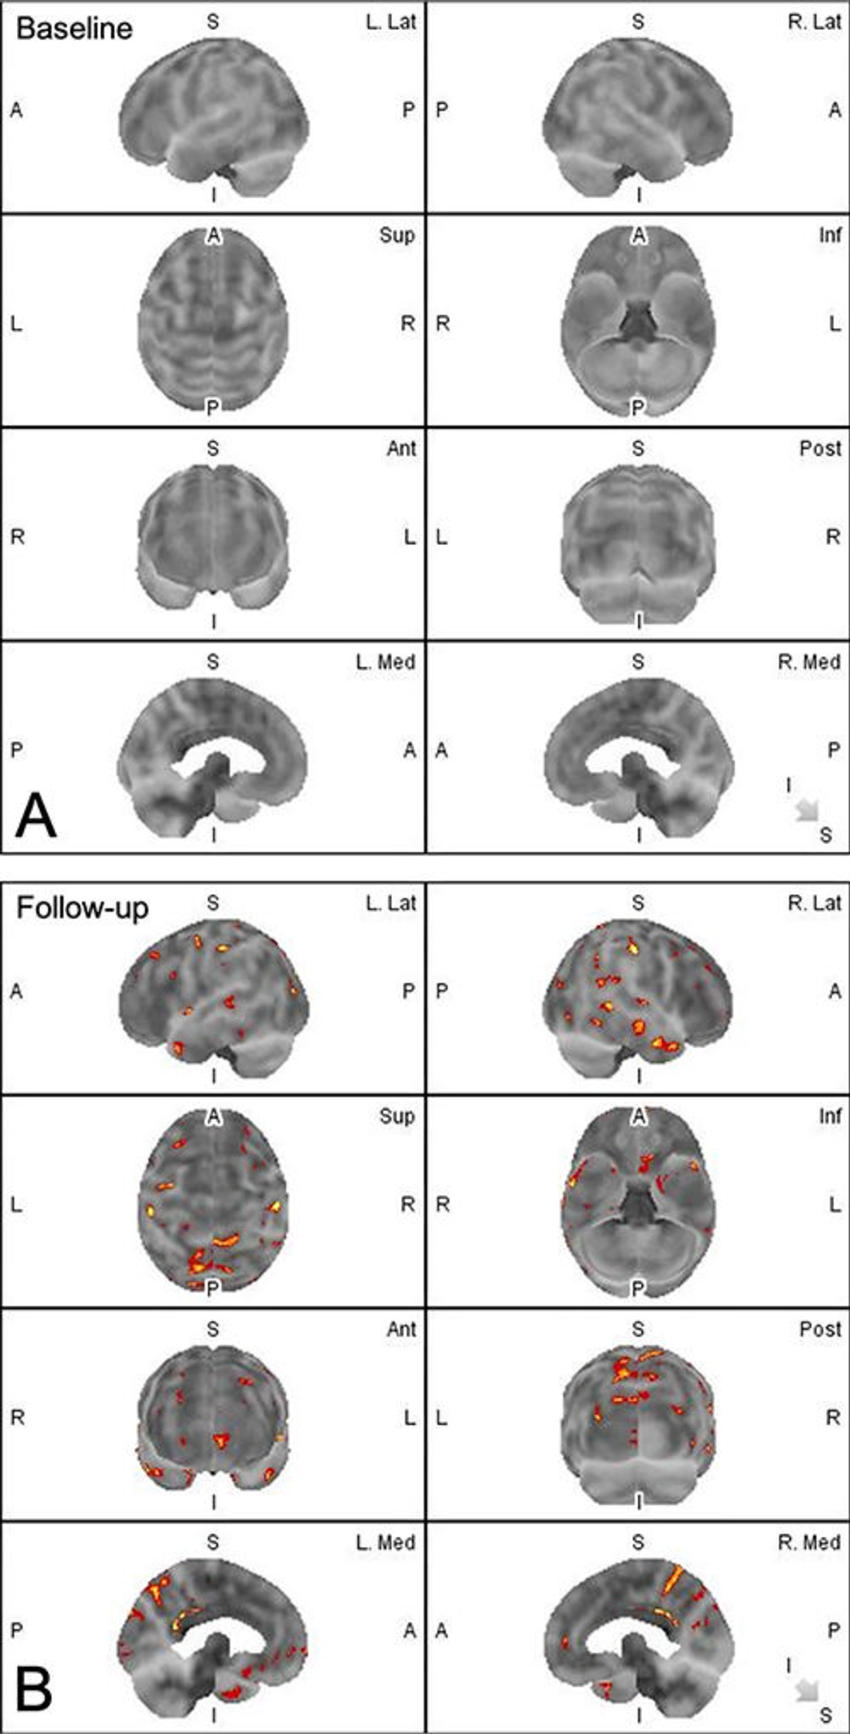

Figure 2. (A) Baseline and (B) follow-up volume-rendered amyloid PET images acquired 5 months apart in a male participant exposed to subconcussive blast injuries. Red clusters identify abnormal amyloid uptake compared with healthy control participants by statistical modeling. (B) Note amyloid deposition at follow-up in the precuneus, posterior cingulum, paracentral lobules, and lateral temporal and inferomedial frontal lobes. A = anterior, Ant = anterior, I = inferior, Inf = inferior, L = left, Lat = lateral, Med = medial, P = posterior, Post = posterior, R = right, S = superior, Sup = superior.